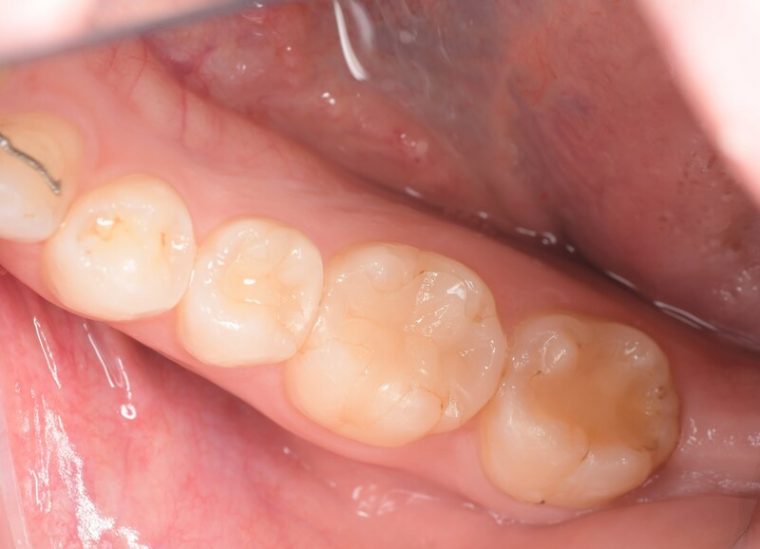

before

症例

年齢・性別 28歳・女性

主訴 右下7番の歯肉の厚みが気になる。

治療内容 歯肉を切除する周辺に麻酔をし余分な歯肉と結合組織を一部切除し歯肉を縫合します。二週間後に抜糸を行います。

治療期間 2週間

治療費 合計 2,000円(保険適用3割負担)

(2023年3月現在)

リスク・副作用 ・歯肉を一部切除する為、数日痛みがでることがあります。

・歯肉切除した歯にしみる症状がでる可能性があります。

特記事項 外科治療の為、当日の運動やお酒など血流がよくなる行動はお控えください。

担当者所見

抜糸の際、術後の痛みはほとんどなく歯肉の厚みがなくなり清掃しやすくなったと患者様がおっしゃっていました。